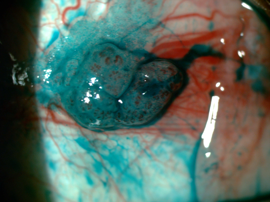

Fig 2. A lesion suspicious for OSSN due to lobulated structure showing abnormal vessel pattern (left) and lissamine green staining (right). Credit: Dr Mo Ziaei

OSSN can range from mild dysplasia to invasive squamous cell carcinoma. Compared to pterygia, lesions suspicious for dysplasia can look more gelatinous, leukoplakic, papilliform or plaque-like and can be more vascularised (presence of a feeder vessel or abnormal blood vessel patterns). Other tests that may help the clinician differentiate between a benign or malignant lesion include the use of Lissamine green staining (Fig 2) or anterior segment OCT examination. There is an abrupt transition from normal epithelium to thickened hyperreflective epithelium in patients with OSSN⁴.